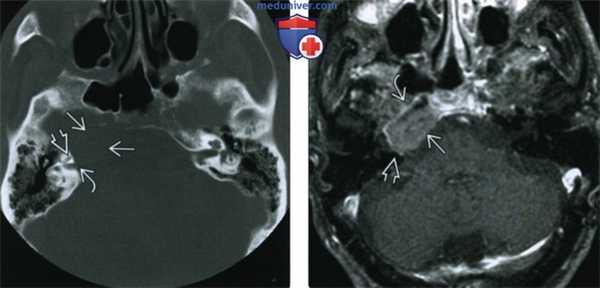

(Слева) При КТ в костном окне в аксиальной проекции у больного миеломной болезнью 72 лет с головными болями и диплопией определяется солитарное литическое объемное образование верхушки пирамиды правой височной кости. Эта плазмоцитома прорастает улитку и внутренний слуховой проход.

(Справа) При МРТ Т1ВИ FS с КУ в аксиальной проекции наблюдается умеренное контрастирование злокачественной плазмоцитомы верхушки пирамиды височной кости. Видно, что опухоль окружает каменистый сегмент внутренней сонной артерии и через эрозию кости прорастает назад, во внутреннее ухо и внутренний слуховой проход.